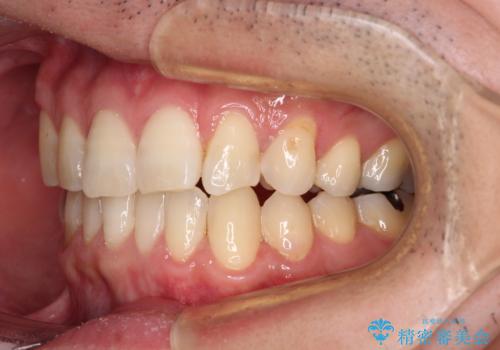

欠損のある歯列 インビザラインで整った歯並びに

- デコボコした前歯をセラミックできれいに揃えたいとのことで来院された患者様です。

歯を削って整えることは簡単ですが、健全な歯を削って後悔してからでは遅いため、矯正治療を提案しました。

はじめは矯正治療の期間が長いことに悩んでいらっしゃいましたが、ある程度整えば満足するだろうとのことで、インビザラインにて矯正治療を行うこととしました。

左上の犬歯が欠損しているため、正中の位置や奥歯の咬み合わせが理想的にならない点を了承していただきました。